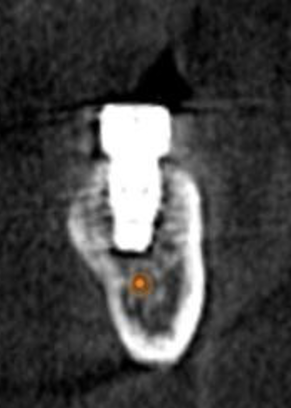

(12.) Postoperative CBCT image of actual implant placement at site No. 21.

Figure 12

(13.) Postoperative CBCT image of actual implant placement at site No. 19.

Figure 13